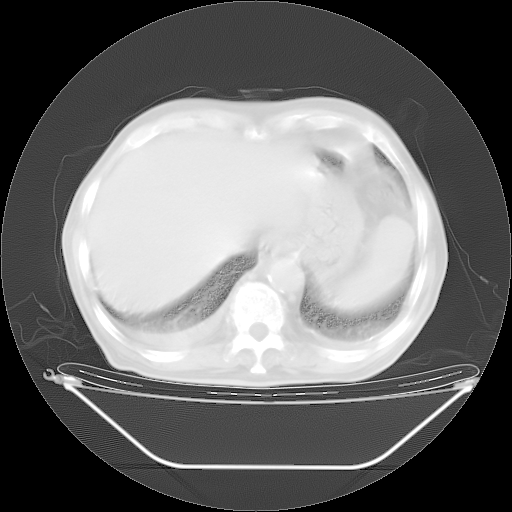

胸腹部CT,诊断意见:左上肺叶钙化灶、左侧胸膜局限性增厚并钙化、胆囊炎。描述部分肺组织呈磨玻璃样改变。

今天复查肺部CT,发现双肺广泛磨玻璃样改变。所以我把3月19日和5月9日相隔50天的肺部CT上传。请大家会诊。

5月9日肺部CT(在4月27日齐鲁医院肺部CT描述部分肺组织磨玻璃样改变,12天后肺组织广泛磨玻璃样改变)

大致读了系列胸部CT:纵隔窗无明显异常,肺窗:从4、27至今:主要是双肺中下野外带可见毛玻璃样改变,目前处于急性肺泡炎阶段,至于原因考虑1、结替组织或胶原血管性疾病所致?2、恶性疾病如恶组在肺部所致的表现或细支气管肺泡癌?3、药物或其它原因如肺蛋白沉着症所致肺泡炎目前不太可能?总之,明天就去请我院的呼吸科、感染科、血液科和临免专家会诊哈。